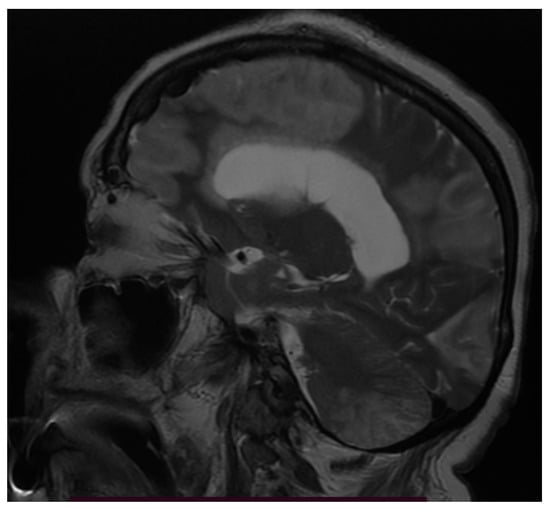

3.3. Neuroimaging